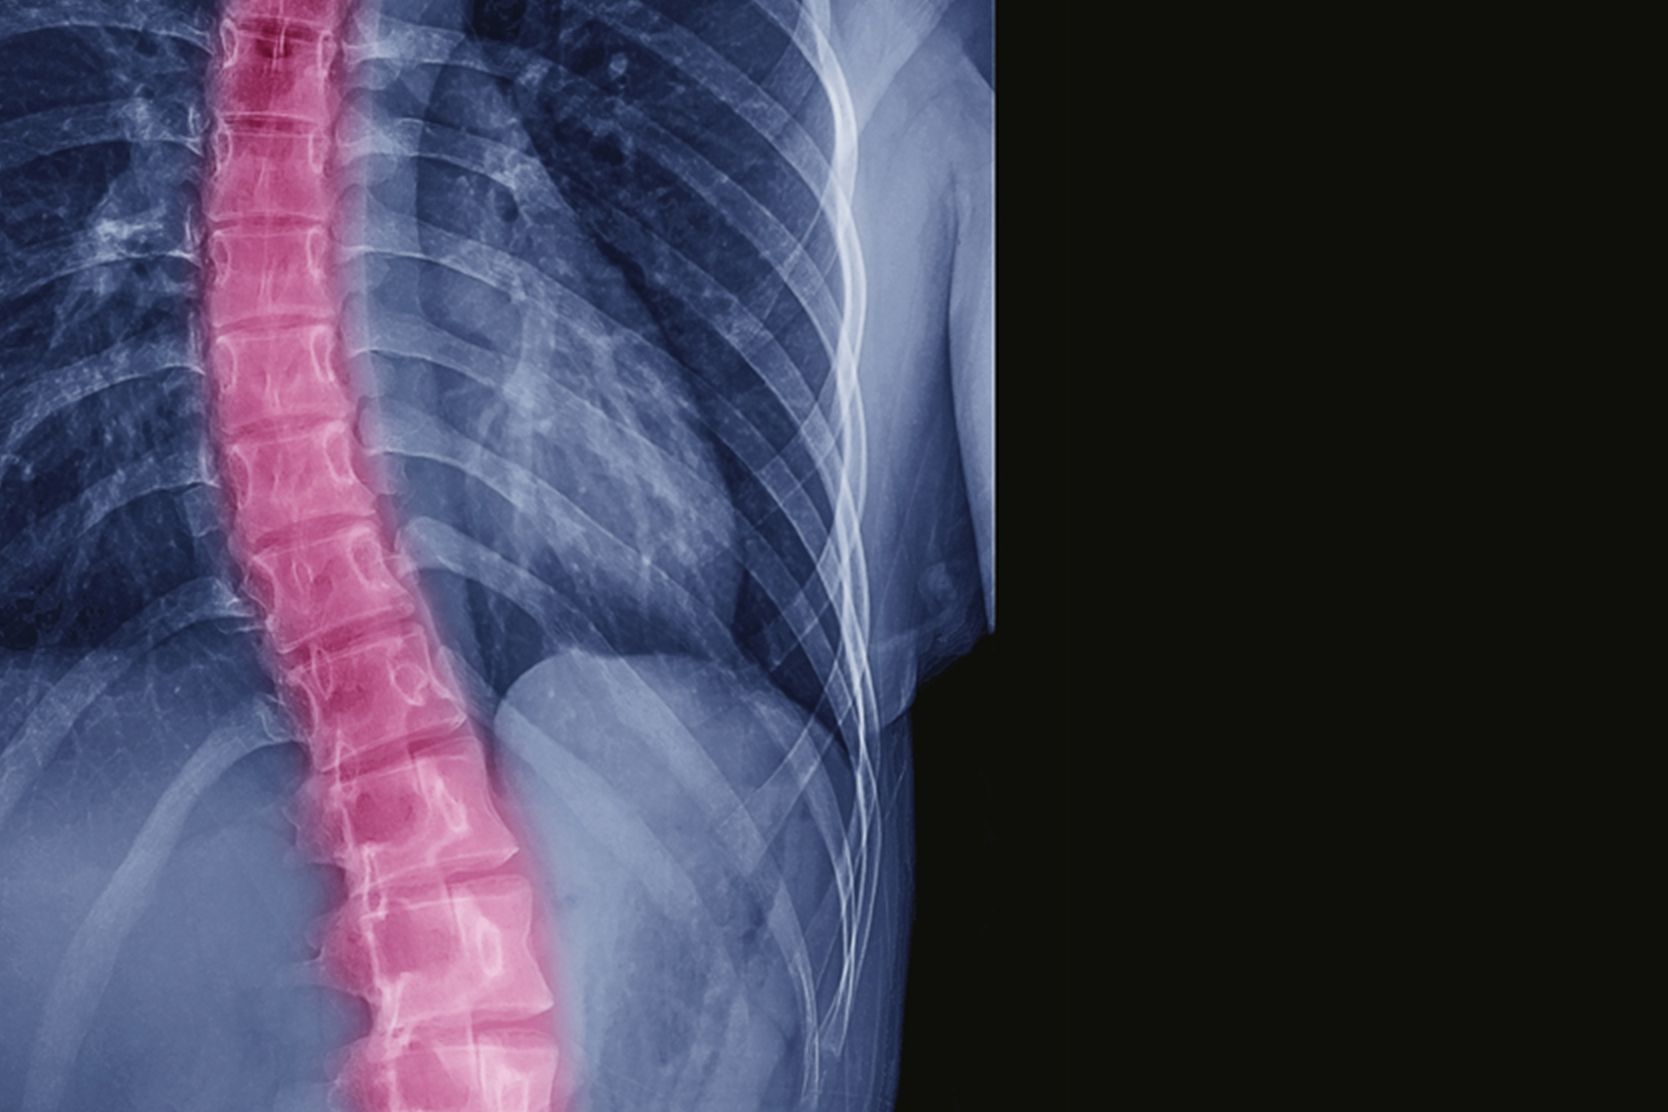

Scoliosis is a curvature of the spine that occurs most often in adolescents, but adults develop the condition too. An estimated 60 percent of the older population have what is known as adult scoliosis. As people live longer and are more active, this number is expected to increase.

Adult scoliosis is most common in people between the ages of 50 and 80. It is characterized by a side-to-side curvature of the spine caused by degeneration of the spine's facet joints, which act as hinges to help the spine bend.

Spinal curvature is measured in degrees. Unlike the slow progression of adolescent scoliosis, adult scoliosis can remain the same, can progress slowly and can progress at higher rates of more than 3 degrees a year. Often, the condition causes significant physical pain and can impact quality of life.

Standing X-rays, from the front and side, will be taken to document the curvature of your spine and to determine how fast the curve is progressing.